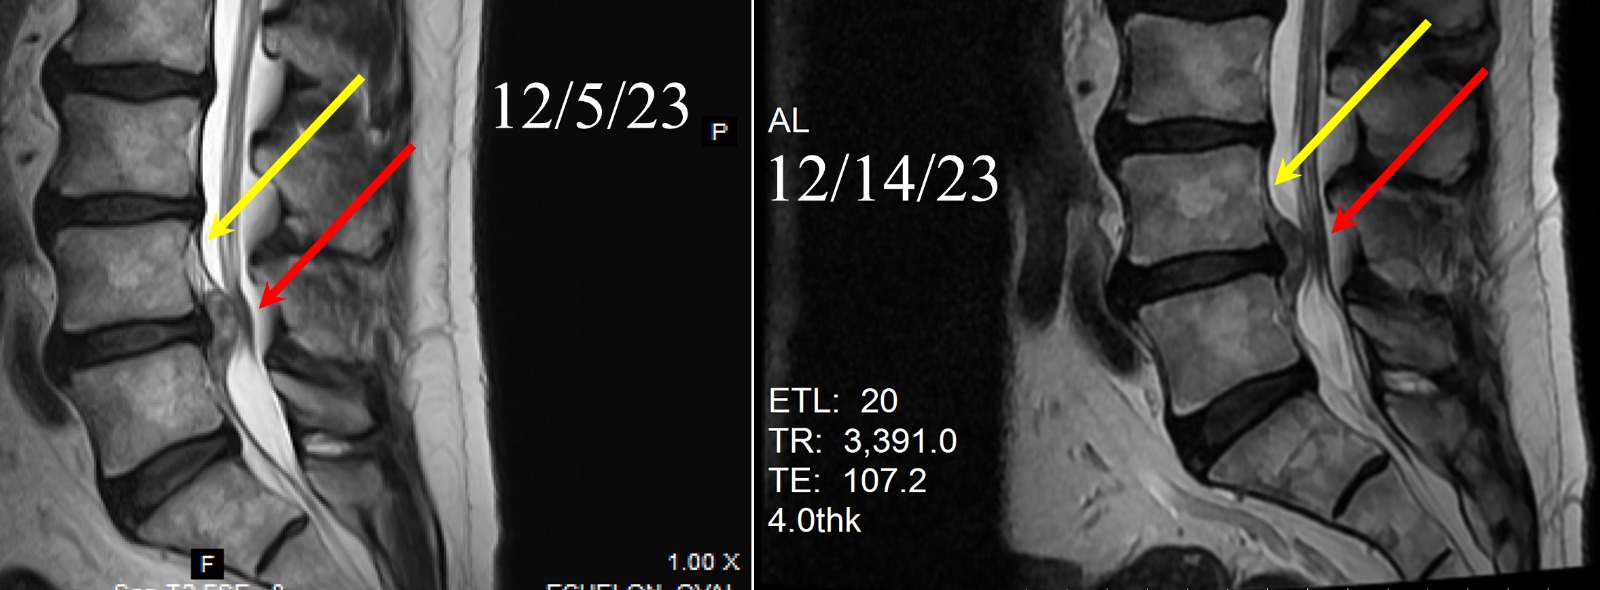

Based on evidence, large disk herniations start to regress by a few millimeters (mm) within 10 days of receiving our proprietary treatments. In this example below, a large disc herniation was found to be compressing on the lower part of the spinal cord called cauda equina causing severe pain symptoms in the patient (Left Image, red arrow). Within 7 days of a SINGLE treatment (treatment date 12/7), the large disc herniation had regressed releasing the free floating fibers of the cauda equina (Right Image, red arrow). The patient not only got immediate pain relief but also effectively avoided surgical treatments, such as open laminectomy and the adverse events that may follow such surgical treatments. Additionally, multiple treatments and repeat injections are NOT required for this specific disc herniation, as the herniation will continue to regress without repeat treatments

By August 2024, MRI of the above patient showed complete resolution (dissolution) of the disk herniation with official radiology reading saying, “the previously visualized disk protrusion (herniation) is no longer visualized.”